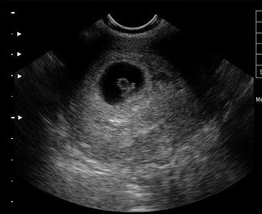

【NO.4】B超检查我要提问.gif

[早孕结果]:同房后20天左右(医院检查,可信度高,结果准确,可判断是否为宫外孕)

方法点评:用B超诊断早孕是较正确可靠的方法。在B型超声波屏上就可显示出子宫内有圆形的光环,又称妊娠环,环内的暗区为羊水,其中还可见有节律的胎心搏动,还可以看到孕囊大小、孕囊位置、还可以看到胎心和胚芽。

医生指出,B超的检查另外一个作用是能确定是宫外孕还是宫内妊娠,胚胎是否存活,这个是其他检查无法比拟的优点。